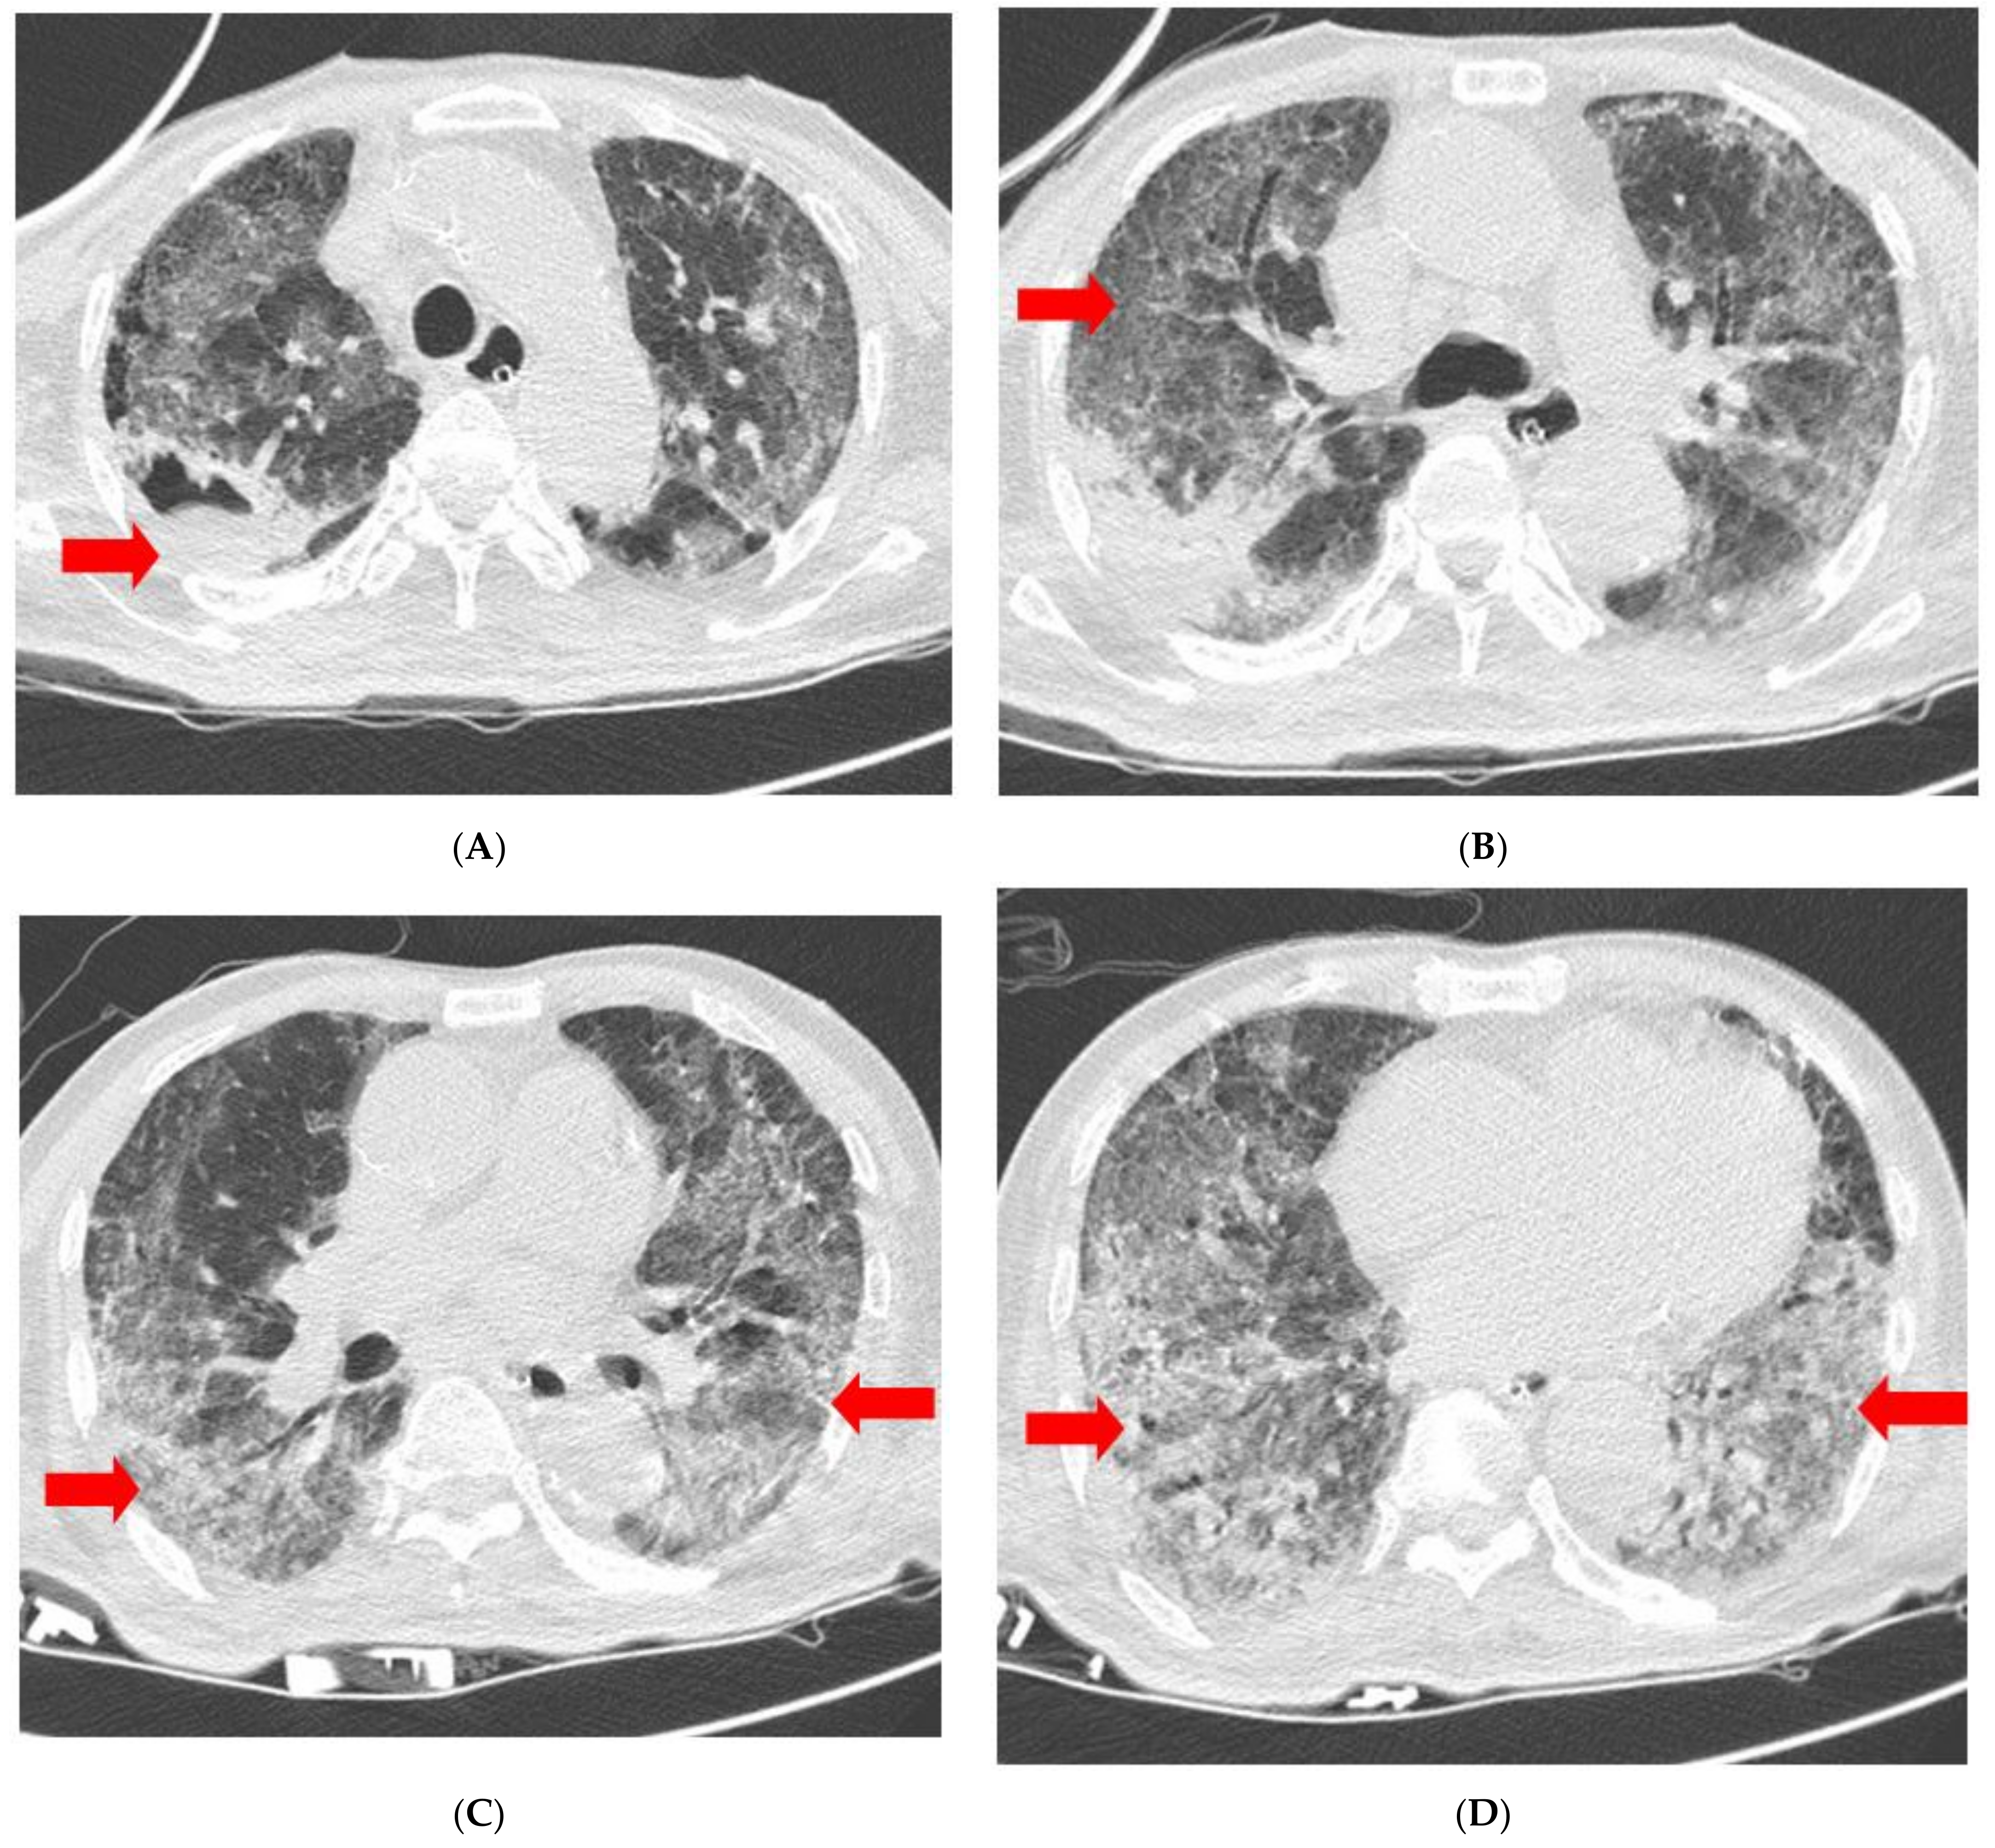

| Chest radiography | GGO in BLLF | Increased GGO | Increased GGO | Decreased GGO | Decreased GGO | Decreased GGO | No interval change | No interval change |